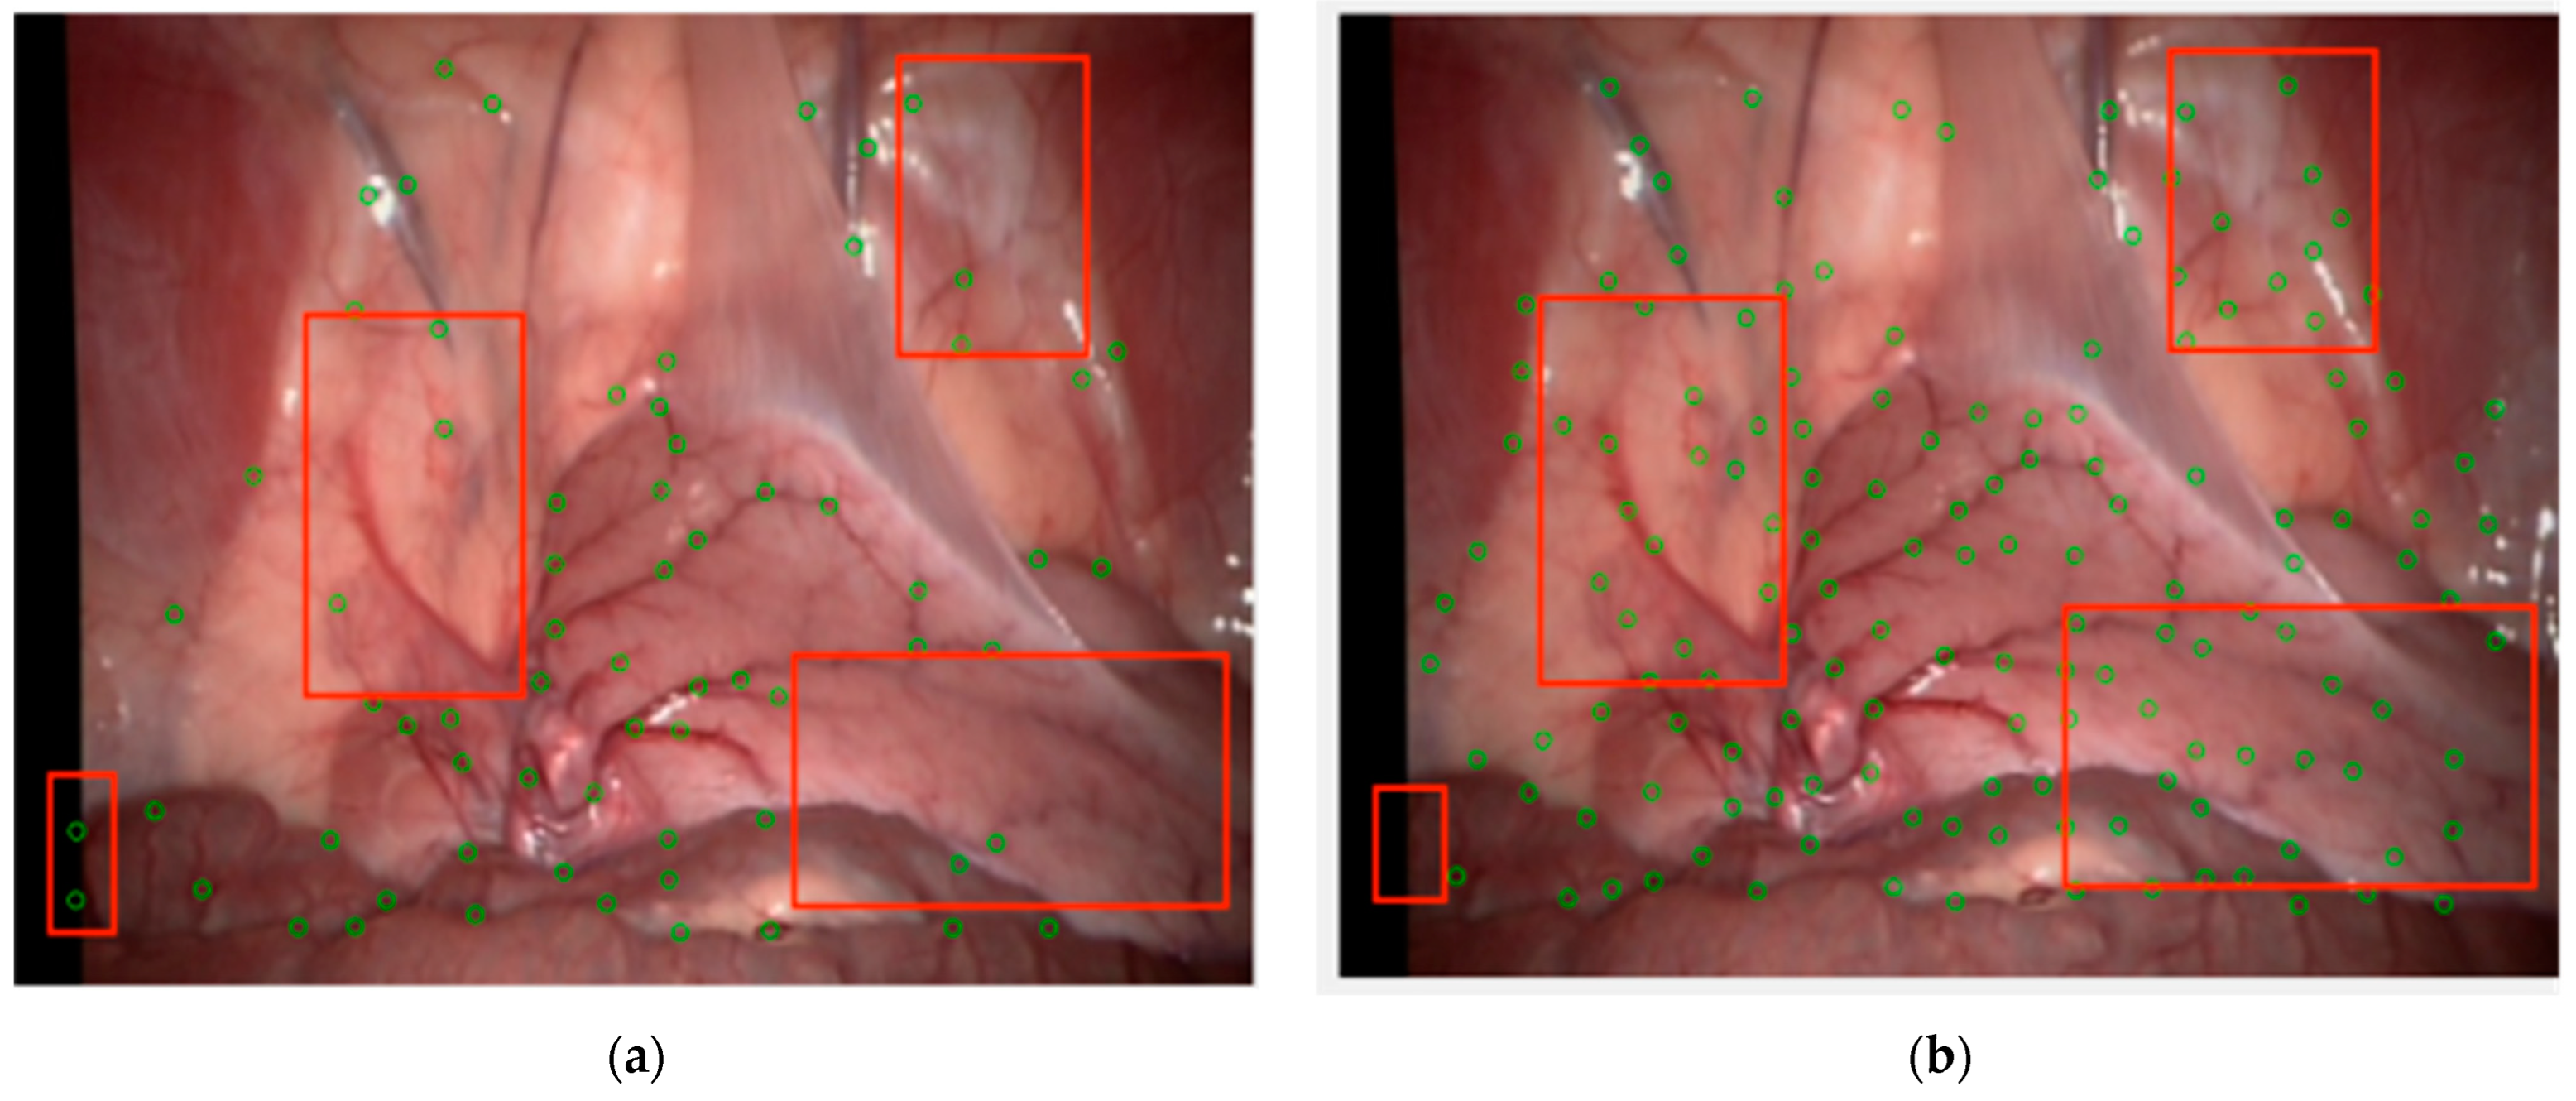

Subjectively, taking images from the Hamlyn data set Rectificed01 as an example, on the basis of enhancing the vascular structure, circles with a radius of 5 and 7 are respectively set for detection and extraction of branch points. Compared with the classical Frangi enhancement algorithm, the results are shown in Figure 10 and the green circles marked the feature points. It can be seen that the method proposed in this paper compensated for the structural measurement differences and uneven responses of the Frangi enhancement method on venous blood vessels and microvessels, suppressed the influence of boundary regions and highlights, solved the problem of generating a uniform response between different vascular structures, and effectively suppressed noise without affecting the connection as shown the regions in the red rectangles. The method proposed in this paper covers the preprocessing framework and the fusion optimization process. Although vascular enhancement is achieved through effective parallel processing, it still affects the overall running speed of the method. The average time of the RBCT is 0.95931 s, while the method in this paper increases it to 1.9515 s.

Figure 10.

Extraction of vascular branch points: (a) after Frangi enhancement; (b) after weighted fusion MFAT enhancement.